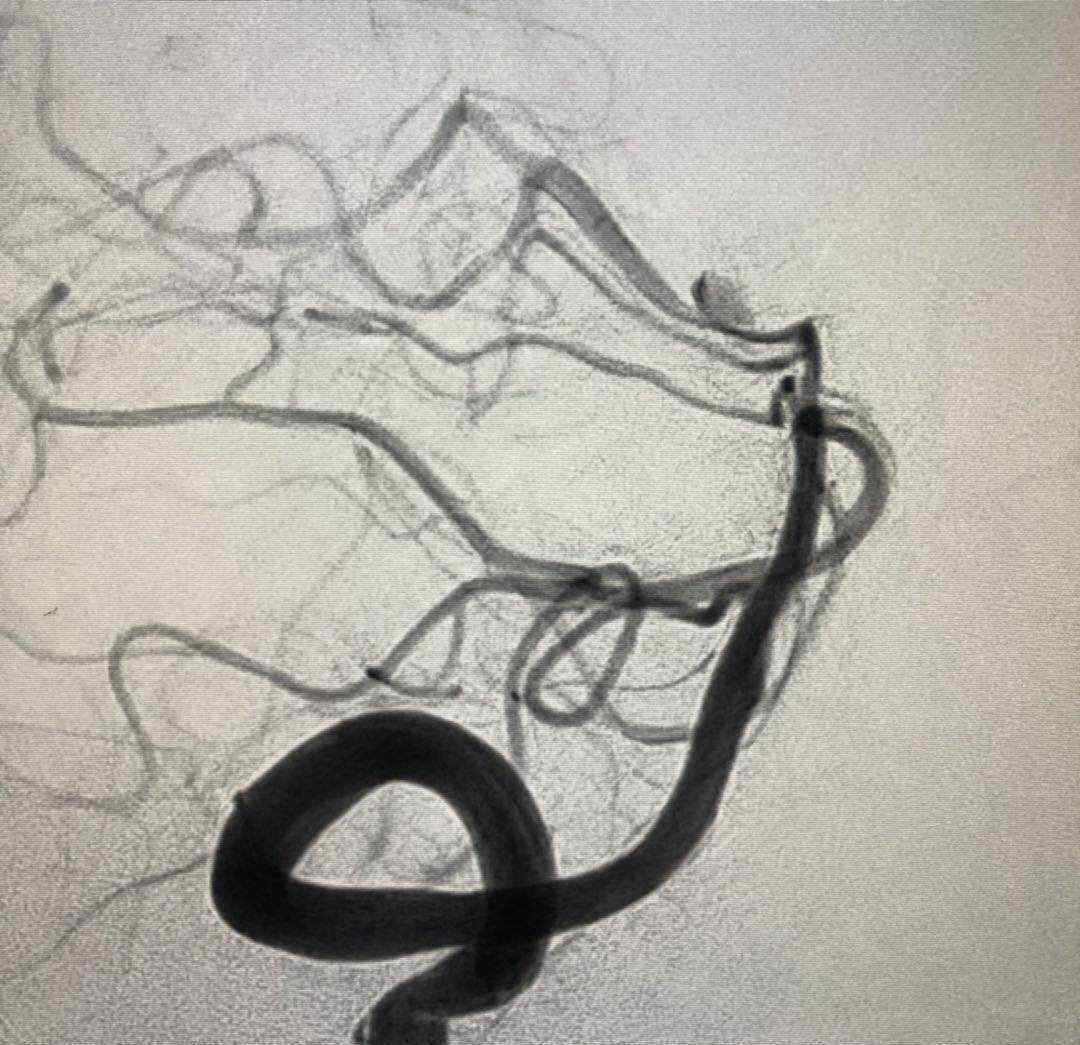

入院后行CTA,考虑左侧后交通动脉瘤。但局部高密度影,考虑动脉瘤破裂出血或巨大动脉瘤附壁血栓可能性大。

考虑为宽基底4.9毫米,大小约为7.9*7.1毫米。

于2019.4.18日行颅内动脉瘤栓塞术